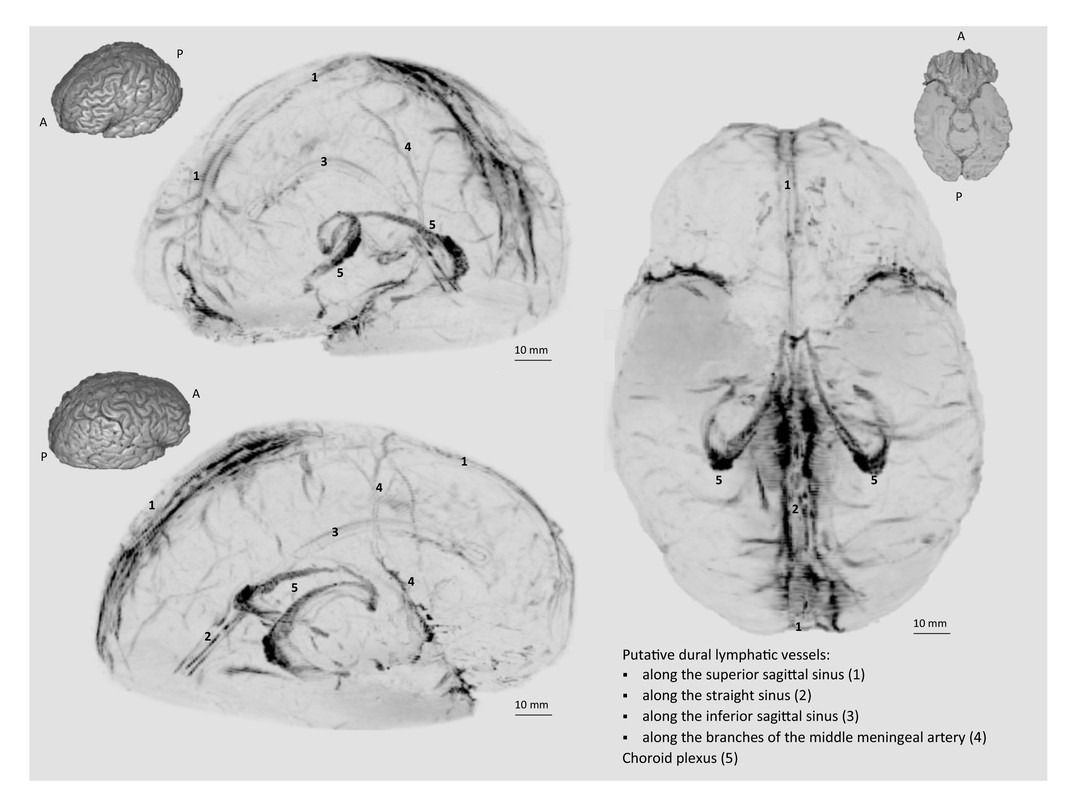

The human brain is a complicated organ that’s difficult to understand, so it’s only natural that we always have more to learn. But recently, researchers at the U.S. National Institute of Neurological Disorders and Stroke published images of a previously undocumented system of vessels that are part of the lymphatic system in the brain. That’s right, up until this very moment many weren’t even positive that these vessels, which transport fluids critical to metabolic and inflammatory processing, existed at all.

Up until the present, not only were these deep-purple vessels largely unheard of, most doctors have been taught that the skull contains no lymphatic vessels. This previous notion however existed in complete contradiction with how the rest of the body works. The lymphatic system both collects and drains fluids, removing waste, facilitating infection response and inflammation, and so much more. In-the-know about the necessity of the lymphatic system of the human brain, it feels like an absurdity in retrospect to think that somehow our brains would not work with the lymphatic system.

In 2015, researchers discovered the “glymphatic system,” or fluids that were found in the brains of both humans and mice that could transport things like glucose and lipids. But at the time, they didn’t know how these fluids might connect and communicate with the rest of the body. This most recent discovery bridges that knowledge gap.

But this discovery doesn’t just identify this system of vessels, it explores how it operates and just how complex and intricate it is. “The study shows that these vessels exist. We haven’t shown that they’re involved in any disease process,” Reich carefully worded, “but it’s reasonable to think that they might be.”